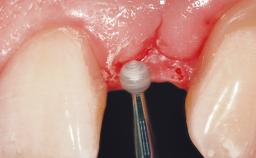

A 30-year-old female patient had lost tooth 21 and was referred to our clinic for consultation and treatment. Due to advanced apical infection, tooth 21 had been extracted two months earlier at another clinic and an acrylic-resin tooth had been bonded to the adjacent teeth. The patient desired implant treatment to avoid any damage to the adjacent natural teeth. While the patient had no history of any systemic disorder, she was a heavy smoker and exhibited medium to advanced periodontitis in the entire jaw. After the initial treatment to achieve a pocket probing depth of less than 4 mm and no bleeding on probing, a decrease in the height of the papillae mesial and distal to the extraction site and overall gingival recession were observed.

Soft Tissue Grafting Simultaneous